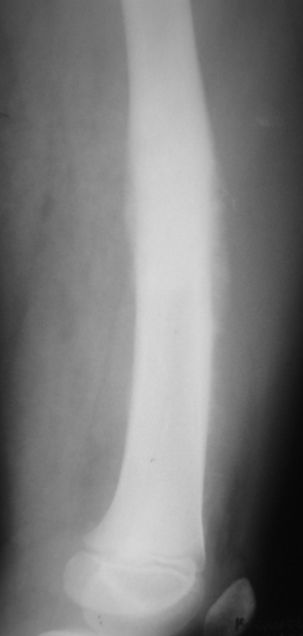

Мальчик 8 лет. Жалобы на боли в левом бедре. Со слов мальчика, ударился бедром несколько недель назад, после чего и начались боли. Выполнили рентгенограммы, затем - КТ (заранее прошу прошение за качество). Диагноз вроде сомнений не вызывает:(

Типичный анамнез, почти всегда упоминание о какой-нибудь, пусть даже малозначимой, травме. Да, ОНА - остеогенная саркома.

Я бы на первое место поставила саркому Юинга. У нас была девочка 5 лет, с подобными изменениями в бедренной кости, только чуть выше, гистологически была саркома Юинга.

Согласен со Шлевой. А дискуссии гасить (смайлы)! Картина достаточно характерная, диагноз более-менее ясен и без патоморфологического подтвержденния, тем более приличия соблюдены - не просто снимки, а снимки + КТ. Так что тем быстрее пациент окажется в специализиованном учреждении, тем лучше.